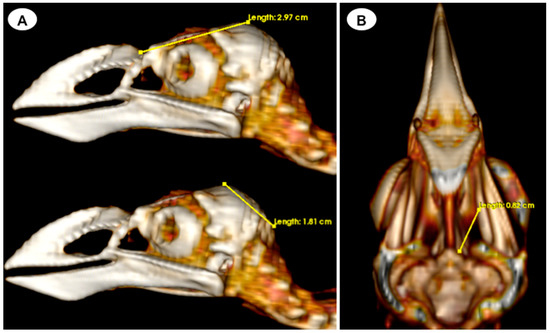

- Three-dimensional reconstruction

- Head length: This measurement is obtained from the centre point of the junction between the beak joint to the prominentia cerebellaris, providing the length of the head (Figure 5A);

- Depth of the orbit: This measurement represents the distance between the midpoint of the orbital diameter and the foramen opticum, indicating the depth of the orbit (Figure 5B).